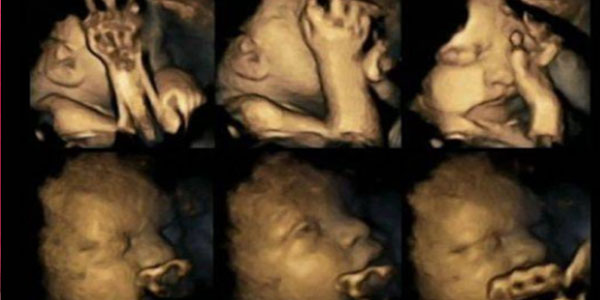

Seorang ahli dari Inggris meneliti wanita merokok dan tidak merokok yang hamil 24 minggu, 28 minggu, 32 minggu dan 36 minggu serta melakukan USG 4D untuk melakukan perbandingan. Hasilnya sangat mengejutkan!

Merokok tidak hanya buruk bagi perkembangan anak dan janin dan kesehatannya, tapi juga memiliki akibat yang sangat fatal! Hasil USG di bawah ini membuktikannya kalau ternyata kebiasaan satu ini membuat bayi di dalam perut sangat menderita!

Ternyata bayi dalam kandungan wanita yang merokok akan lebih sering memegang bagian hidung dan mulutnya daripada mereka yang tidak merokok, ini juga ternyata berpengaruh pada pertumbuhan janin.

Janin yang normal, semakin dekat dengan hari kelahirannya, maka akan mengurangi gerakan di dalam perut ibunya, sedangkan janin dari ibu yang merokok justru akan menyebabkan sistem saraf bayi terganggu dan responnya lebih lambat, akhirnya ini akan berdampak pada pertumbuhan bayi kelak.